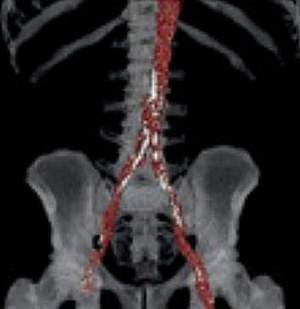

The team used CT scans of the abdomen previously taken for colorectal cancer screening, from more than 9,200 men and women without symptomatic heart disease. Participants had an average age of 57. The AI programs measured calcification in the aortic artery, muscle density, the ratio of fat deep in the body to that under the skin, liver fat, and bone-mineral density as seen on the scans.

AI scores of calcification in the aortic artery alone were better than the FRS at predicting heart disease risk. All five measures alone were more predictive than BMI taken at the start of the study. In general, combining more than one of the AI measurements increased the ability to predict later heart disease risk from an abdominal scan. Adding the FRS to the AI measurements did not improve their predictive performance.